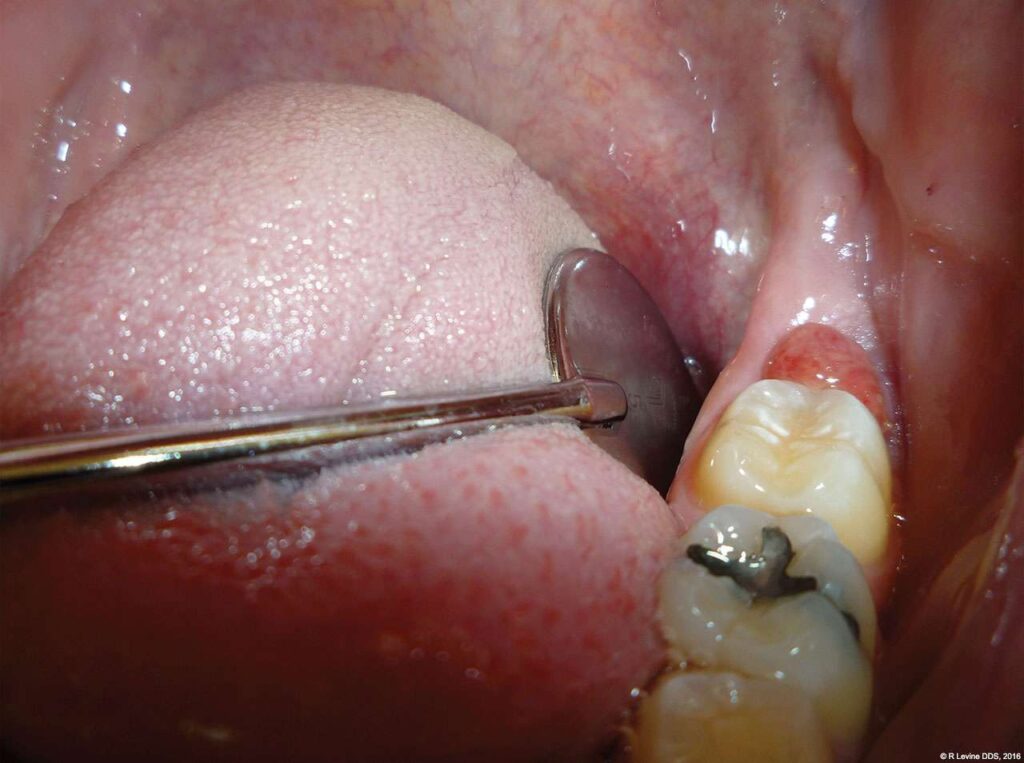

The patient presented with a raised, inflamed, painful operculum distal to the left mandibular second molar (Figure 3). The lesion was red, edematous, and bled easily. A periodontal pocket on the distal of the second molar was > 6 mm deep. There was no evidence of abscess.

- The angled handpiece of the CO2 laser was held perpendicular to the target lesion (Figure 4) and the ablation of the inflamed tissue began (Figure 5). The dental surgeon was careful to avoid contact between the laser beam and the tooth enamel. (Note: In this case, the inflamed tissue was located distally from the involved molar. There was no direct contact of the beam with the tooth, as the surgeon was careful not to hit the enamel. However, if an operculum covers part of the tooth, an adaptive tool (for example, a wax spatula) needs to be inserted between the tissue and the tooth to prevent possible damage. For an inexperienced CO2 laser surgeon, it is important and highly recommended to always shield the tooth during the procedure.[6])